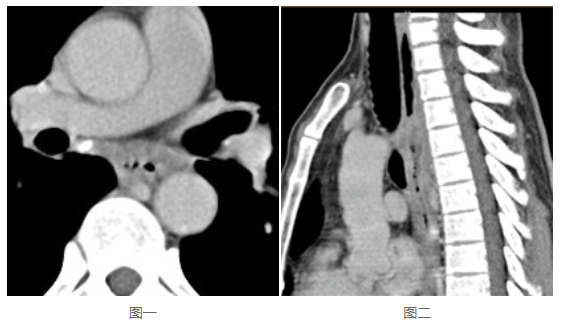

幾乎所有PACS軟件都具備縮放、平移、調(diào)窗、測(cè)量、電影功能,這部分功能適用于平片、DSA等;也具備分窗、MPR、MIP、VR功能,適用于CT、MR。因此PACS工作站適用于絕大部分影像的后處理,是閱片寫報(bào)告的基本要求。那么,這些功能在移動(dòng)端,采用B/S方式使用時(shí),是不是仍然具備?是不是還適用于絕大部分類型的影像?如果是,那么可以認(rèn)為具備閱片寫報(bào)告的功能要求;如果不是,顯然,對(duì)于部分類型的影像,閱片寫報(bào)告則相對(duì)困難,甚至可能無法判斷。看下這兩張圖:

這是同一病灶的不同視角,圖一是橫斷位,圖二是矢狀位。很明顯,圖二對(duì)于食管的侵蝕顯示得更為直觀。這應(yīng)該就是《浙江省數(shù)字影像服務(wù)專家共識(shí)》明確要求“保存檢查時(shí)生成的各種成像體位的完整序列影像”的原因。那么,如果PACS在存儲(chǔ)影像時(shí)僅僅存儲(chǔ)了橫斷位,就一定需要影像軟件本身能將矢狀位影像重建出來。